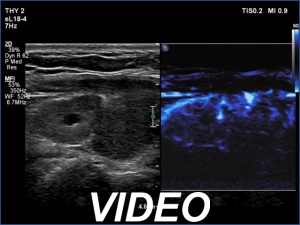

First examination (first row of images):

Clinical data: A 67-year-old woman was referred for evaluation of a newly diagnosed nodular goiter and hypothyroidism. The patient first noticed difficulties in swallowing several months ago.

Palpation: a firm nodule in the right lobe.

Laboratory tests: TSH 5.21 mIU/L, aTPO 821 U/mL.

Ultrasonography. The thyroid was hypoechoic. There was a large, irregular, echonormal mass in the right lobe. The lesion presented both intranodular and perinodular vascularity. The left lobe was decreased in size.

Cytology resulted in oxyphilic tumor.

A right lobectomy was performed. Histopathology disclosed Hashimoto's thyroiditis and benign hyperplastic nodules with extensive oxyphilic metaplasia.